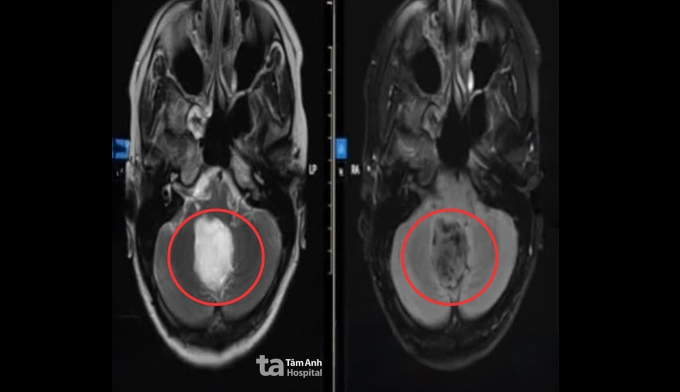

Triệu chứng của chị Trang xuất hiện vài tháng trước, thi thoảng có cảm giác như điện giật ở gáy, sau tai, đôi khi lan lên đỉnh đầu. Cơn đau đến rồi tự hết nên chị nghĩ do mệt mỏi căng thẳng, đến khi đau đầu dữ dội, yếu nhẹ tay trái và tâm trạng bồn chồn, lo lắng khó giải thích, chị mới đến Bệnh viện Đa khoa Tâm Anh TP HCM. Kết quả chụp MRI 3 Tesla cho thấy một u nang kích thước khoảng 4 cm ở vùng lỗ Magendie, hố sau, nằm sát thân não. U nang đã chèn ép thùy nhộng tiểu não và mặt sau thân não, làm hẹp đường lưu thông dịch não tủy, gây giãn nhẹ hệ thống não thất.

Ảnh chụp MRI u thân não của chị Trang. Ảnh: Bệnh viện Đa khoa Tâm Anh

Sau phẫu thuật, chị Trang tỉnh táo, tiếp xúc tốt, sức cơ tay trái cải thiện. Ảnh CT sọ não hậu phẫu cho thấy các cấu trúc não trở về vị trí bình thường, tụ khí và dịch trong hố sau lượng ít. Một tuần sau mổ, người bệnh ổn định, lưu viện theo dõi và bắt đầu tập vật lý trị liệu, phục hồi chức năng. Dự kiến sau khoảng ba tuần, chị có thể trở lại sinh hoạt bình thường và được tái khám định kỳ để theo dõi nguy cơ tái phát u.